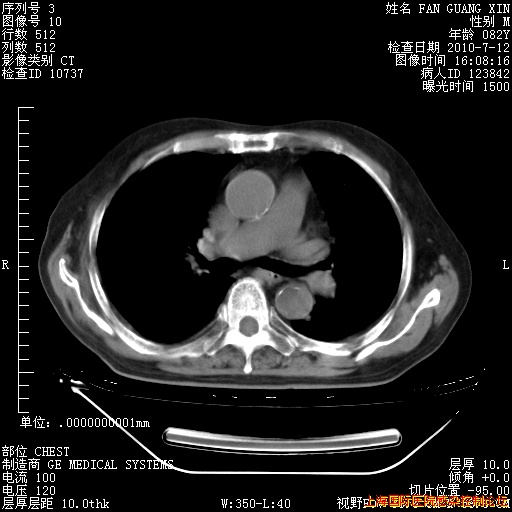

6月12日纵膈窗